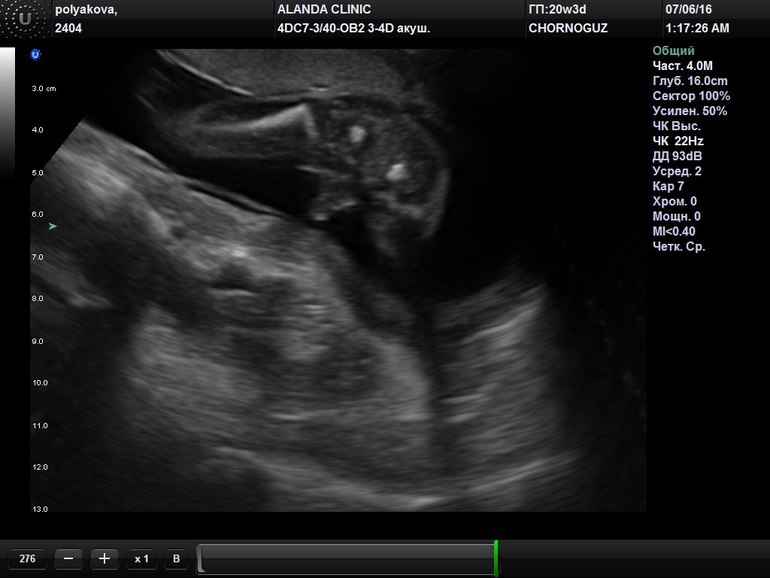

Наш второй скрининг-узи 3d, и у нас будет...

Пол малыша Еще один хулиган!)

Не умеем похоже делать девочек, снова голубой кружок!)

Все отлично, все параметры в норме, придраться не к чему!

А вот и наш хоботок:

Там прям было видно мужское достоинство?) по идее же 3d ... В марте видимо мальчиков раздавали, я тоже так доченьку ждала так уверена была, но на 2-м скрининге врач спокойно сказала- мальчик) теперь ждем не Машеньку, а Захарика) хотя я так растерялась, что даже не попросила показать где там мальчик то)))

Ну у мальчиков там сразу все видно, ошибки быть не может!😄 Дважды убедилась в этом! На втором скрининге точно видно, да и в 14 неделек нам увидели перчик, но я еще сомневалась из-за срока! Первого сына хоботок уже в 16 недель показали)))